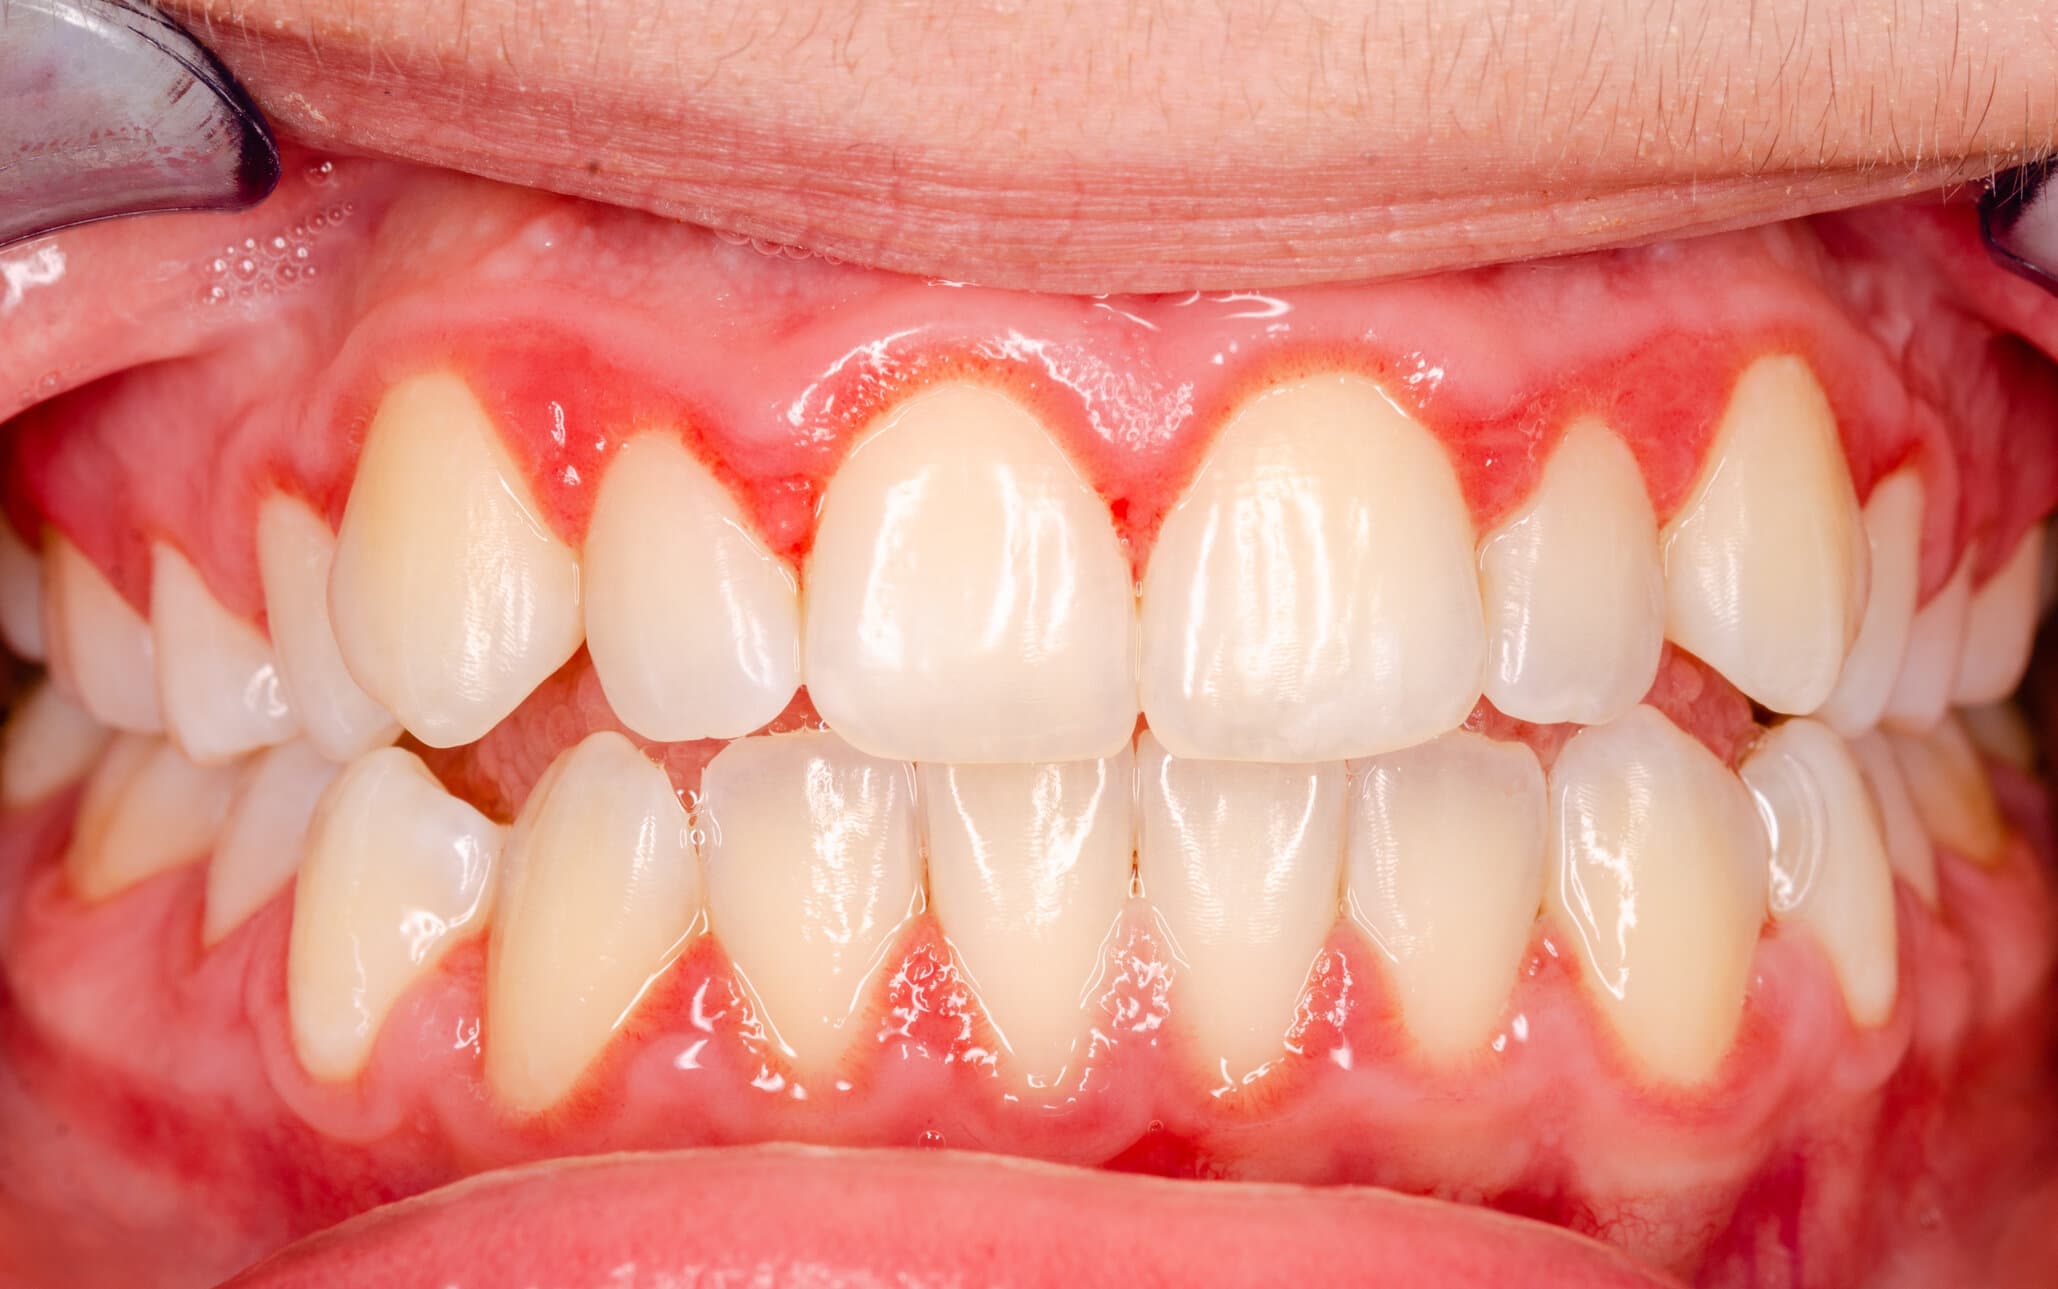

Gum Inflammation

Poor oral hygiene or conditions like gingivitis can cause swollen gums, making them more visible.

Gum Contouring (Gingivectomy)

A minor surgical procedure where excess gum tissue is removed to reveal more of the teeth.